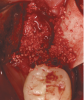

The patient shown in Figure 1 had presented after significant endodontic-related abscesses reduced the height of both buccal and lingual plates of bone. Covering the biphasic calcium sulfate (BPCS) graft with a dense polytetraflouroethylene (PTFE) barrier for 3 weeks enhanced healing in the site. Clinically, it is apparent that the ridge volume was maintained over 5 years and supported keratinized tissue (Figure 2). Most importantly, there was, on histologic evaluation, 58% vital bone, with no remnants of the bone replacement graft material (Figure 3).

Fig 2. Patient in Figure 1 who received BPCS graft shown 5 years after prosthetic loading of the implant.

Figure 2